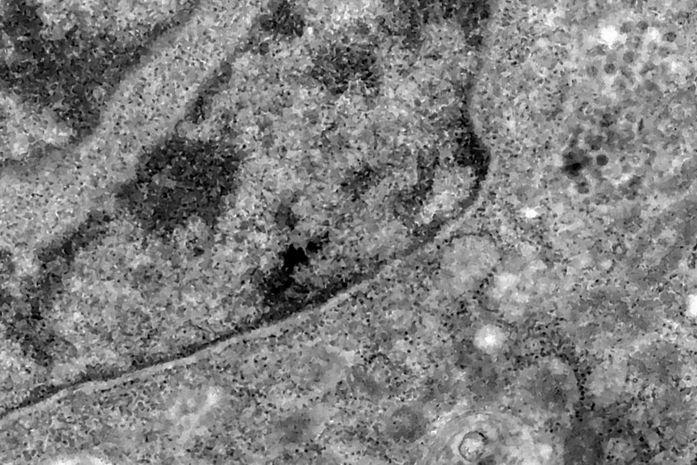

Nos casos analisados, constatou-se que a variante é portadora de dezenas de mutações genéticas que podem afetar os índices de contágio e de letalidade. A OMS, entretanto, afirmou que ainda não há estudos suficientes para afirmar as propriedades da Ômicron, mas que já existem esforços científicos acelerados para estudar as amostras. Um time de cientistas de universidades da África do Sul está decodificando o genoma da Ômicron, juntamente com dezenas de outras variantes do novo coronavírus.

Tulio de Oliveira, diretor do Centro para Respostas e Inovações Epidêmicas da universidade de KwaZulu-Natal, afirmou em coletiva de imprensa que a variante Ômicron possui “uma constelação incomum de mutações”. A variante Delta, por exemplo, possuía duas mutações em relação à cepa original do novo coronavírus, enquanto a Ômicron possui cerca de 50 - 30 delas localizadas na proteína Spike, responsável por infectar células saudáveis, explicou o brasileiro.